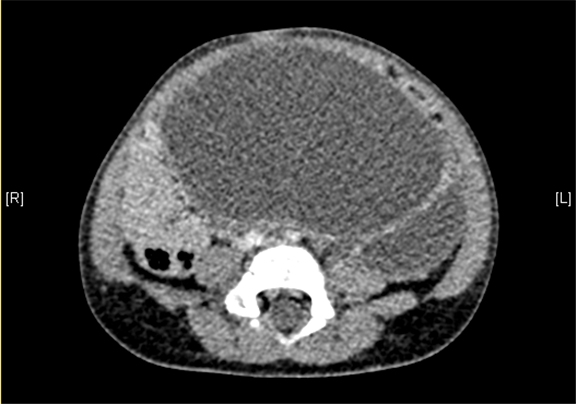

腹部三维动态CT:腹腔巨大囊性占位性病变,考虑肠系膜来源良性病变可能性大,腹腔肠系膜淋巴管瘤?

术前CT检查:

静脉期